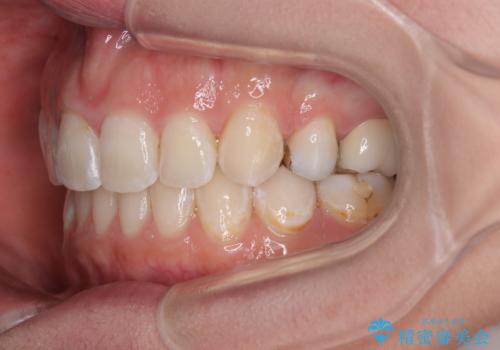

第二小臼歯抜歯はイレギュラーな治療手段であり、治療期間が延びる傾向にありますが、予定よりも早い2年間で終えることができました。